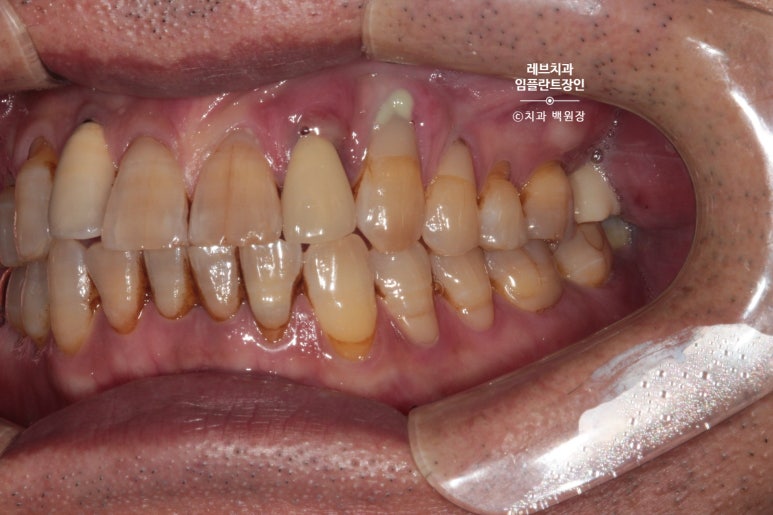

왼쪽 송곳니와 앞니가 흔들리고 고름이 나요.

왼쪽 위 송곳니 (앞니)에서 고름이 나온다는 말씀을 하시던 환자분입니다.

보시면 가만히 있어도 치아와 잇몸 사이에서 고름이 올라오는 것을 보실 수 있어요..

흡연을 좋아하시던 분이었고, 만성 치주염이 심해져서 치주농양까지 진행된 상태입니다.

그렇게 흔들림이 심했던 두 앞니를 뽑고,

한 달 뒤 임플란트 2개를 심어드렸습니다.

광범위한 뼈이식도 함께!